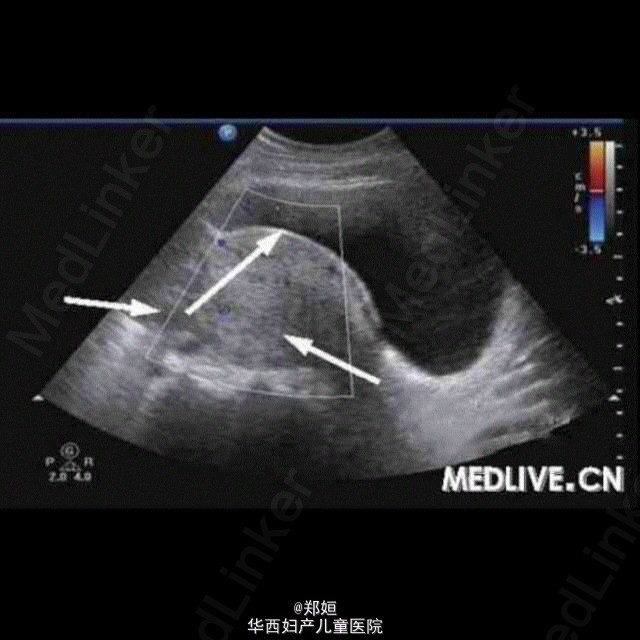

病历资料:女,34岁,6年前体检发现左附件区有一直径为2 cm的肿物,因肿物体积较小而未治疗。5年前患者无明显诱因地出现月经期腹痛 ,伴腰酸腹胀逐渐加重,须服止痛药缓解,B超复查显示,盆腔肿物体积增大。超声检查:子宫肌层回声欠均匀,子宫后壁肌间隐约可见3.8 cm×3.5 cm×3.7 cm中等回声包块,边界欠清,点状血流信号(图1)。右附件可见6.7 cm×5.8 cm×5.3 cm囊性包块,边界清,外形规则, 内为液性暗区伴细密光点,囊壁可见点状血流信号(图2和图3);子宫左上方可见6.1 cm×4.5 cm×4.6 cm囊性包块,边界清,外形尚规则 ,内为液性暗区伴细密光点,内可见分隔,隔壁可见条状血流信号(图4)。 诊断:子宫增大;子宫腺肌症;双附件区囊性包块。 术中所见:子宫前位,宫体球形,质硬;子宫后壁外突瘤核,界限不清。双侧卵巢均囊性增大,囊肿内为巧克力样物质,均为多房,与阔韧 带后叶、乙状结肠和子宫后壁粘连。 http://case.medlive.cn/obgyn/case-article/show-46213_207.html